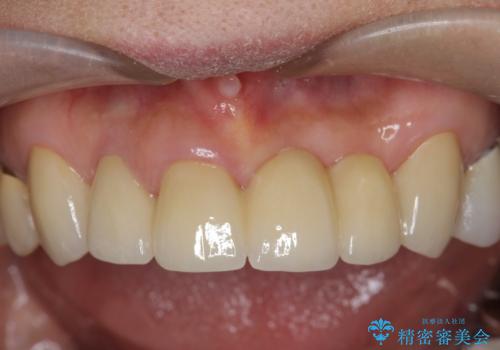

転んで前歯が折れた 前歯のジルコニアブリッジ治療

抜歯後の見た目改善として深い咬合関係であることからインプラントは避け、ブリッジで補綴治療を行っていくこととしました。

- 72.6万円(仮歯・ジルコニアクラウン×6)費用は治療当時の料金となります

元々の噛み合わせが深く(ディープバイト)、転んで顎を強打したことで上顎前歯2本が根元から折れてしまい抜歯をしなければいけない状況となってしまいました。

今後前歯への負担を減らすためにナイトガードマウスピースを使用していただき歯の保存に努めていきます。